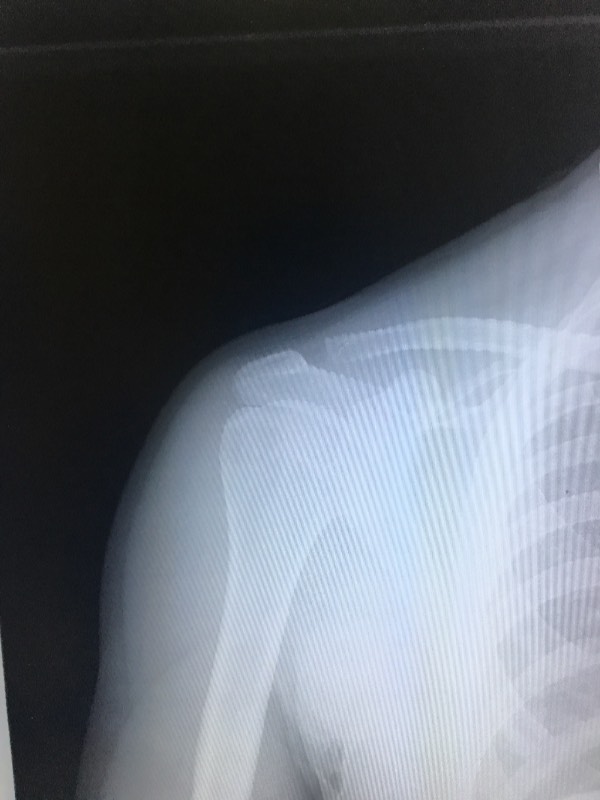

При осмотре врач проверит чувствительность, периферический пульс в поврежденной конечности, проверит наличие активных движений. Таким пациентам показана рентгенография в двух проекциях, КТ, УЗИ пораженного сустава.